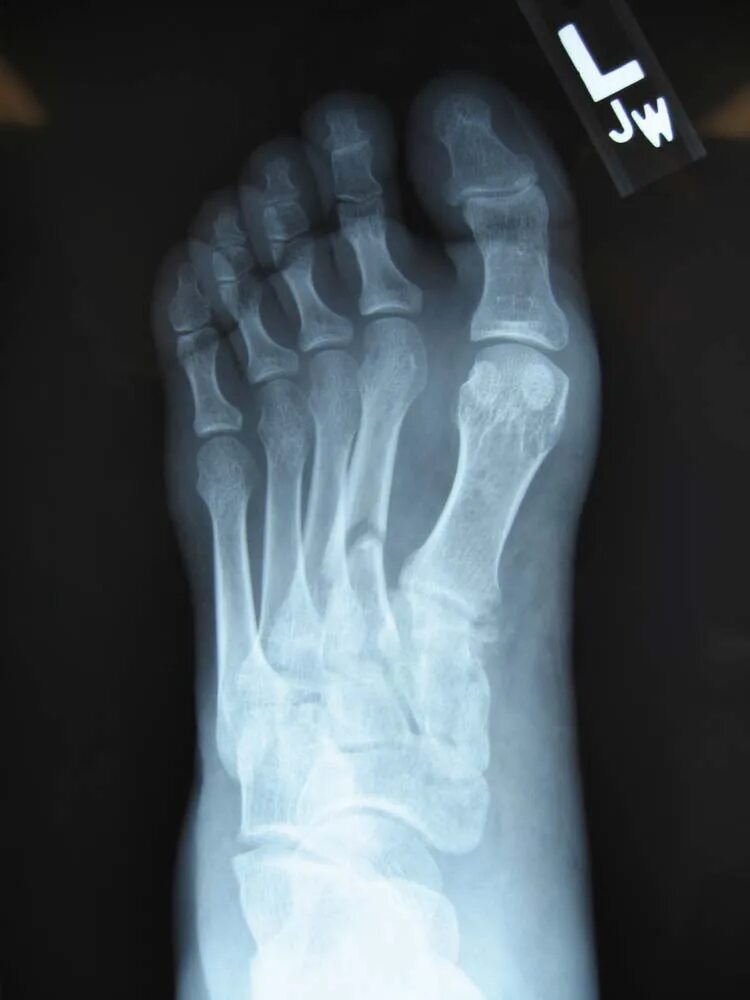

Трещина в кости ноги сколько